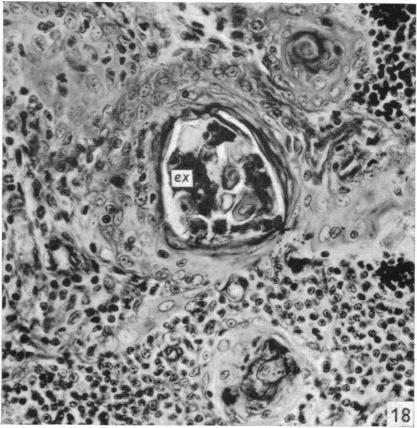

The effect of castration, oestrogens, testosterone and the oestrous cycle on the cortical epithelium of the thymus in male and female rats.

J Anat. 1968 Jun;103(Pt 1):113-33.